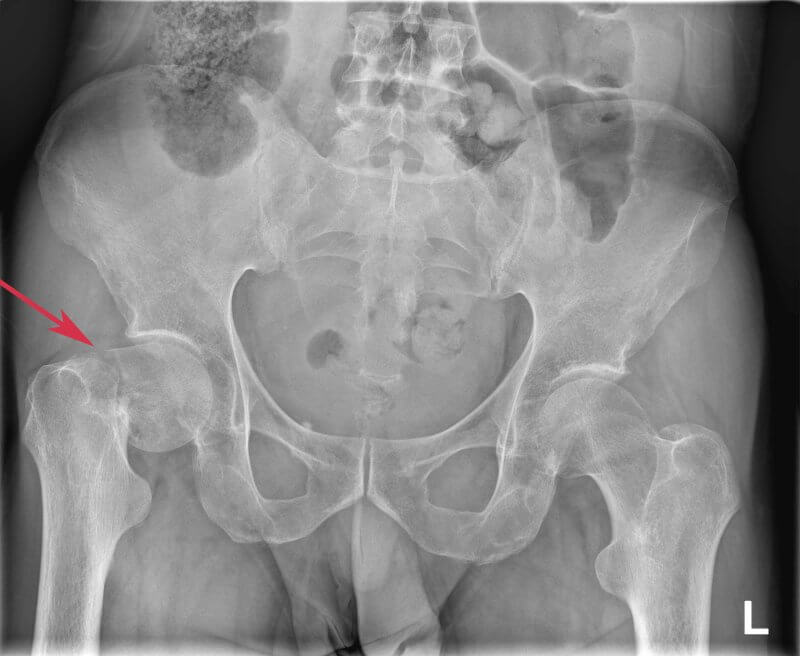

Jak wygląda diagnostyka złamania szyjki kości udowej?

Diagnostyka złamania szyjki kości udowej ma na celu potwierdzenie złamania, ocenę jego typu, przemieszczenia i zaplanowanie leczenia. Rozpoczyna się od dokładnego wywiadu lekarskiego i badania fizykalnego. Pacjent zgłasza silny ból w pachwinie lub biodrze, trudności w poruszaniu się, a także charakterystyczne ustawienie kończyny – skróconej i obróconej na zewnątrz. Te objawy już na wstępie sugerują złamanie. Aby potwierdzić diagnozę, wykonuje się zdjęcie rentgenowskie (RTG) miednicy i biodra, które uwidocznia miejsce urazu i ocenia, czy doszło do przemieszczenia kości. Gdy złamanie nie jest widoczne na zdjęciu, a ból i objawy utrzymują się, lekarz zleca bardziej precyzyjne badania – tomografię komputerową (CT), a również rezonans magnetyczny (MRI). Dzięki tym metodom postawienie diagnozy jest szybkie i dokładne, co ma kluczowe znaczenie dla dalszego leczenia i uniknięcia powikłań.